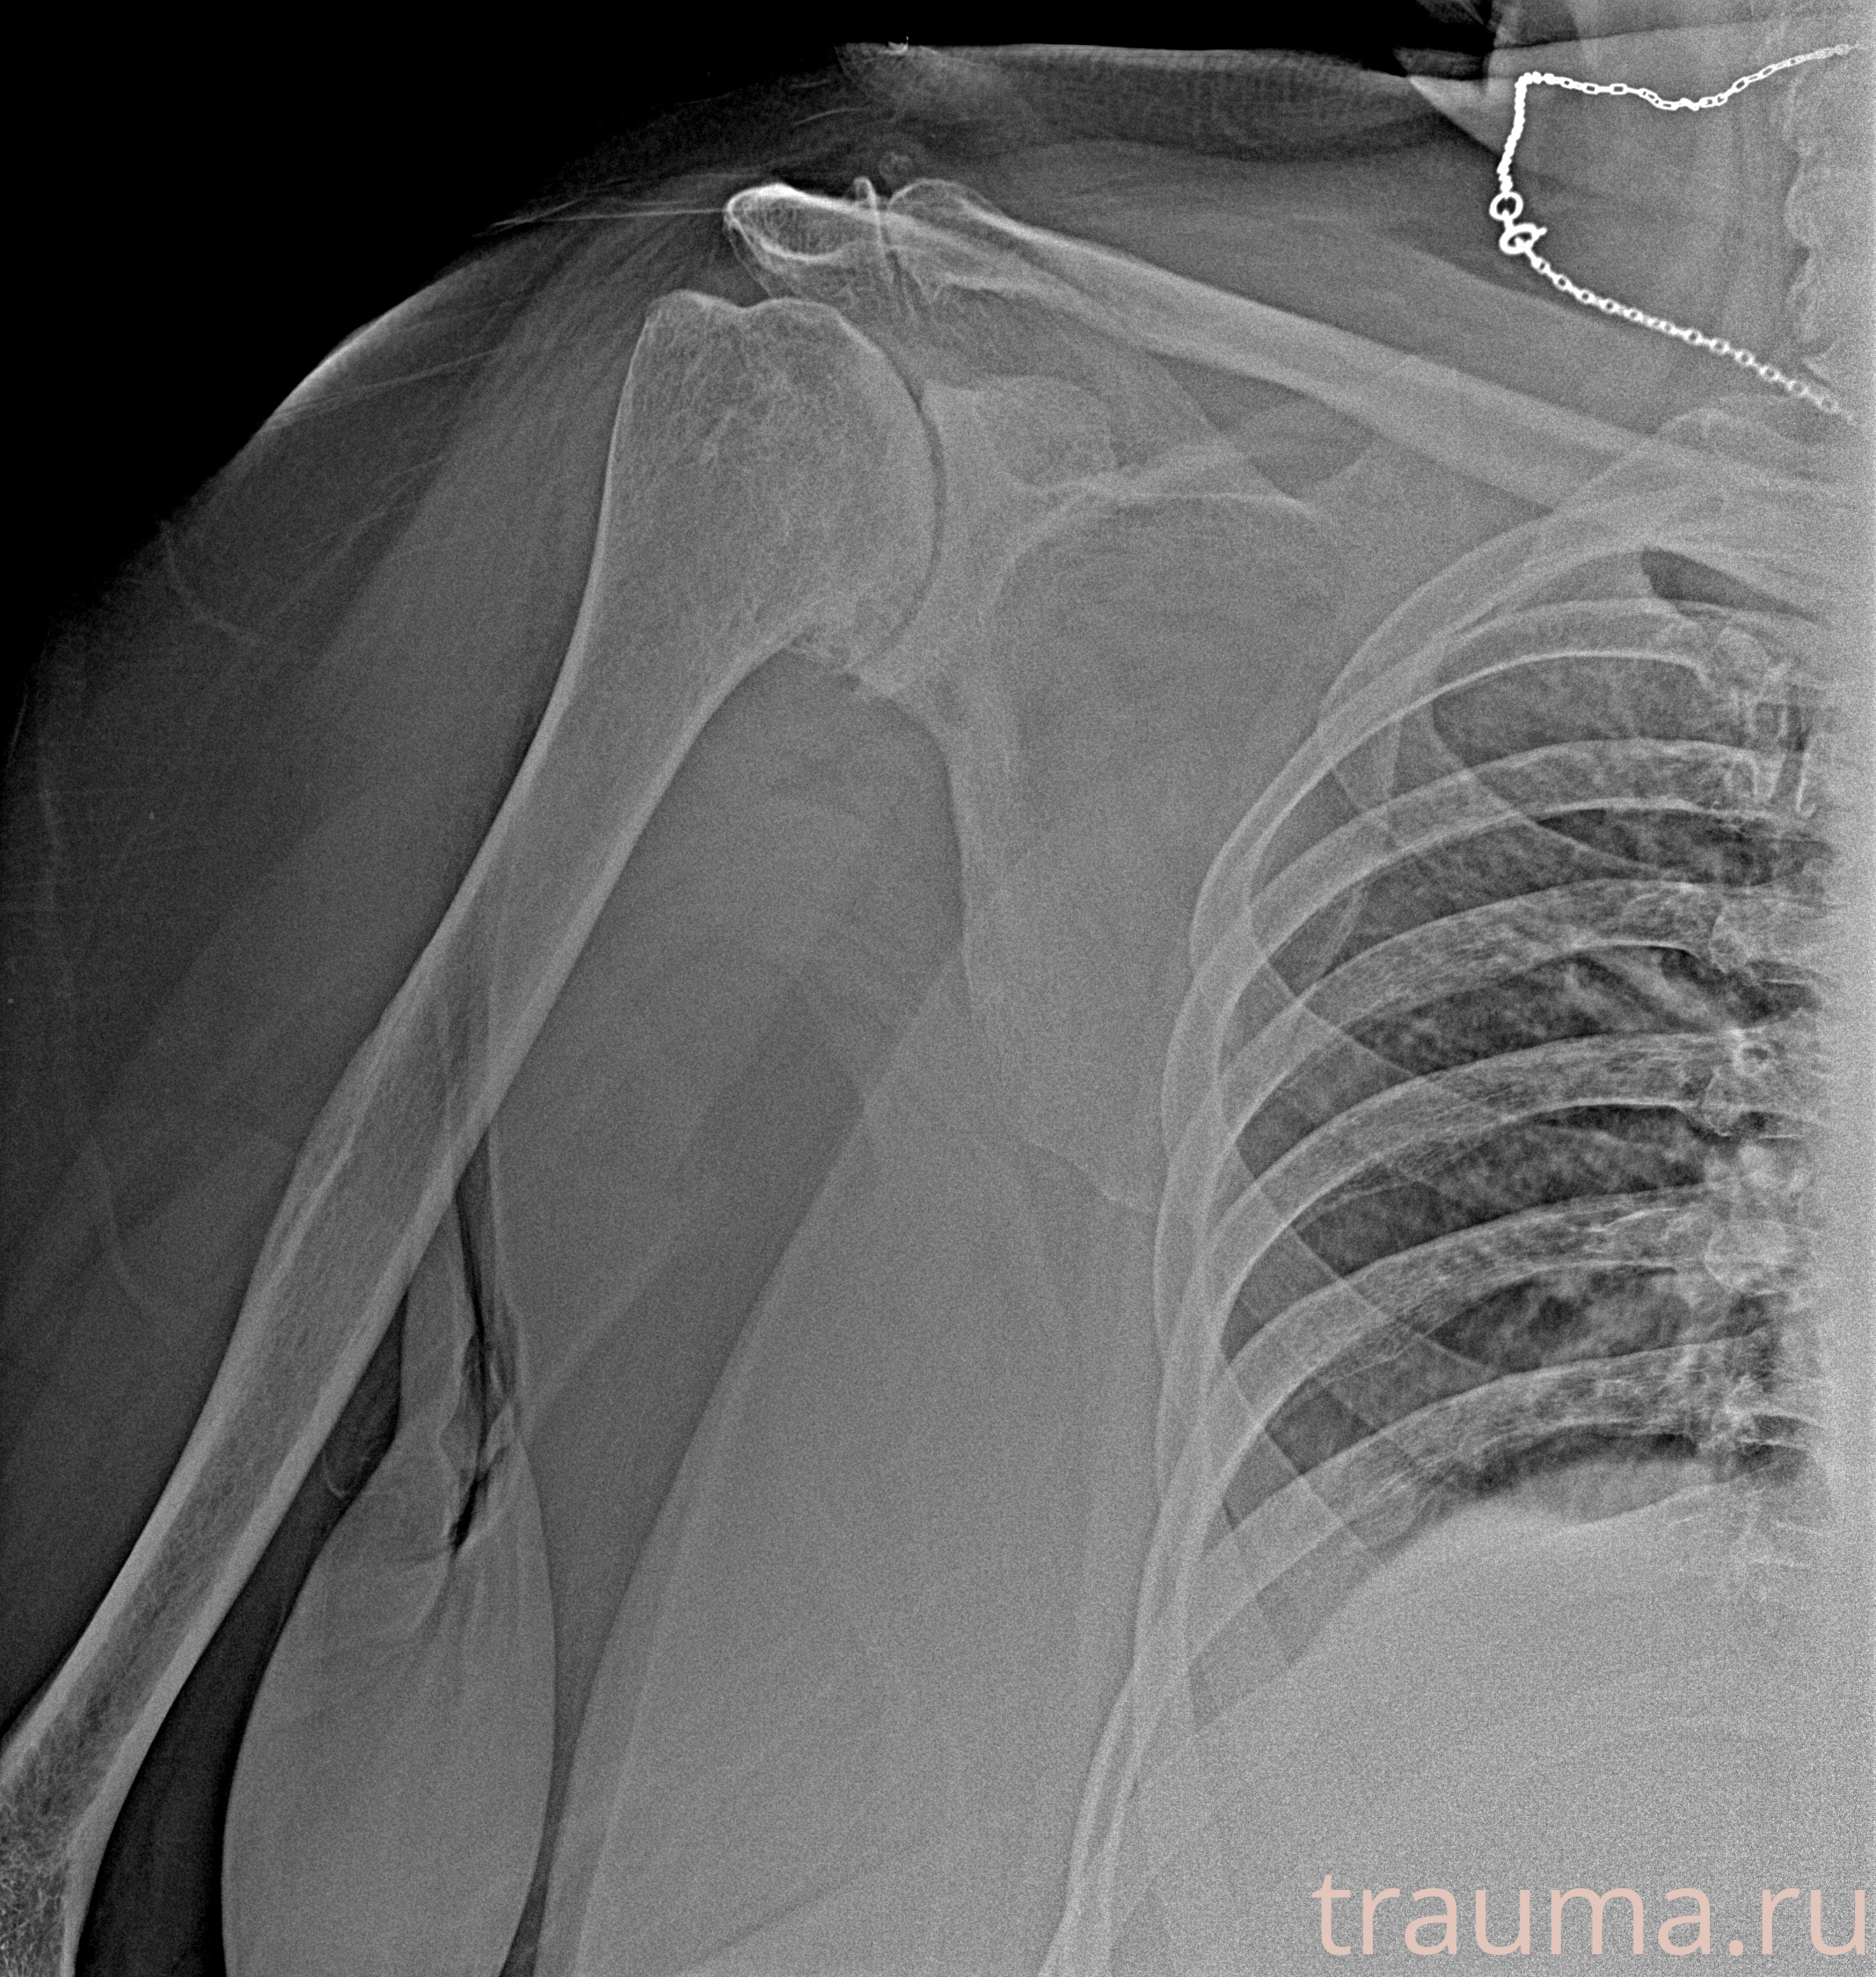

Рентгенограммы

Рентген на дому: по вашему адресу приезжает врач-рентгенолог, травматолог-ортопед с мобильным рентгеновским аппаратом, проводит диагностику травмы или заболевания, делает необходимые рентгенограммы, дает рекомендации по дальнейшему лечению. Получить качественные снимки в домашних условиях возможно благодаря уникальной методике, разработанной МосРентген Центром для института  Склифосовского